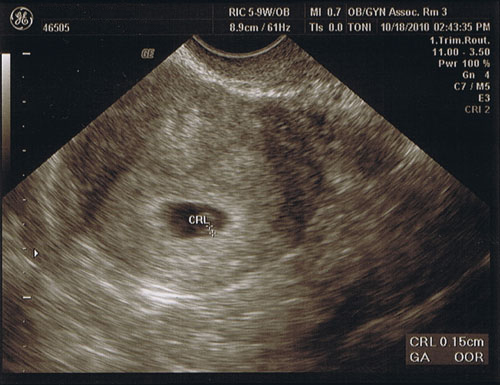

Sunday started the 10th week

Sunday started the 10th week.

The due date is June 19th, and we should probably be finding out the sex at the end of January / beginning of February. Until then we’ve tossed around a few nicknames to refer to the baby as. While Tok’ra was an awesome suggestion (and not by me, mind you) we settled on Nugget.